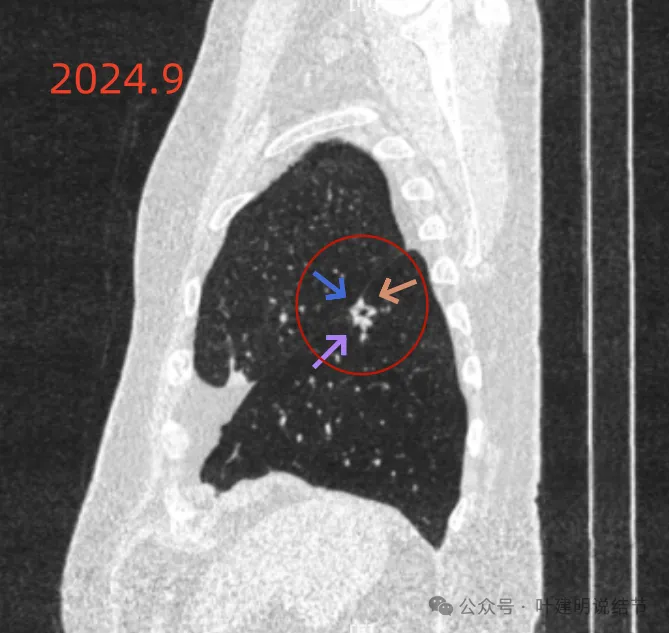

再看2024年9月时的影像:

病灶出现,紧贴叶间裂,有小血管走向病灶侧。

中间有空腔,叶裂侧实性并牵拉叶间裂。

囊腔灶、轮廓清、小血管进入囊壁、囊壁厚薄不均、叶间胸膜牵拉。

表面不平、混合密度、囊腔壁厚薄不均、内壁不光滑、有细支气管扩张通气征。

明显壁厚薄不均的囊腔灶,囊壁基本实性,表面不平,内壁不光滑,且邻近叶间裂并牵拉叶裂。

表面毛糙不平,部分区域有点像锯齿状。

表面不平细毛刺,中间空腔欠光滑、囊壁厚薄不均。

上图囊壁较厚,密度较高,轮廓与边界较清。

病灶边上也有多发小空泡样征,说明病灶有收缩力或对周围结构有影响。

上图显得像混合密度伴偏心空腔征。

上图是病灶边缘部位有血管走向病灶侧,并达病灶的地方有异常增粗。

冠状位见病灶基本实性,小血管进入明显,囊壁厚薄不均,囊腔内壁不光滑,表面浅分叶。

矢状位显示较强的收缩力的样子,表面明显棘突的样子,而且囊壁密度杂乱,伴浅分叶征以及胸膜牵拉征。